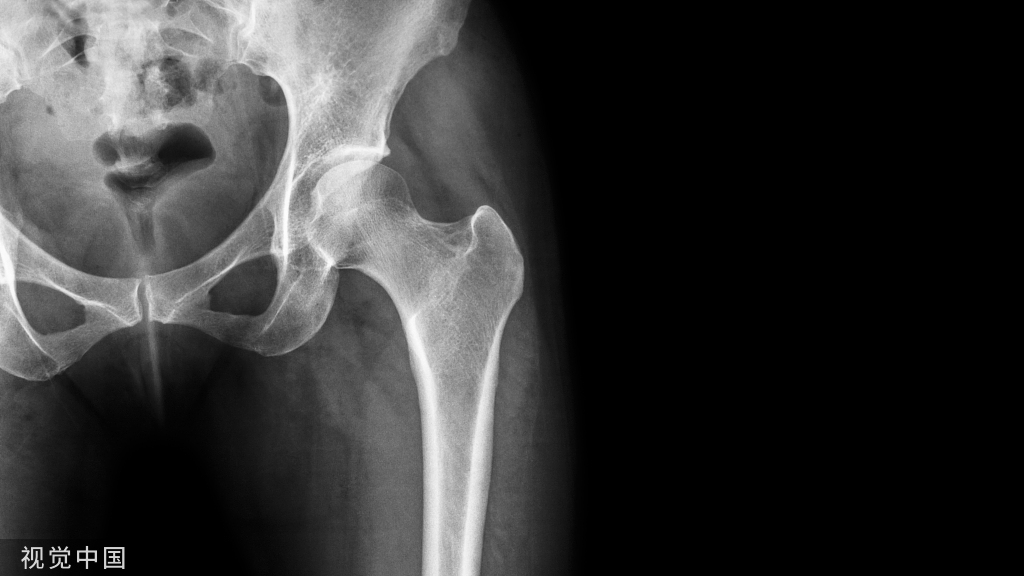

这一次有了明显变化,双侧坏死的面积明显缩小,骨密度增高。病情稳定以后,治疗的间隔时间就可以逐渐拉长,主要依靠药物和锻炼。2年复查: